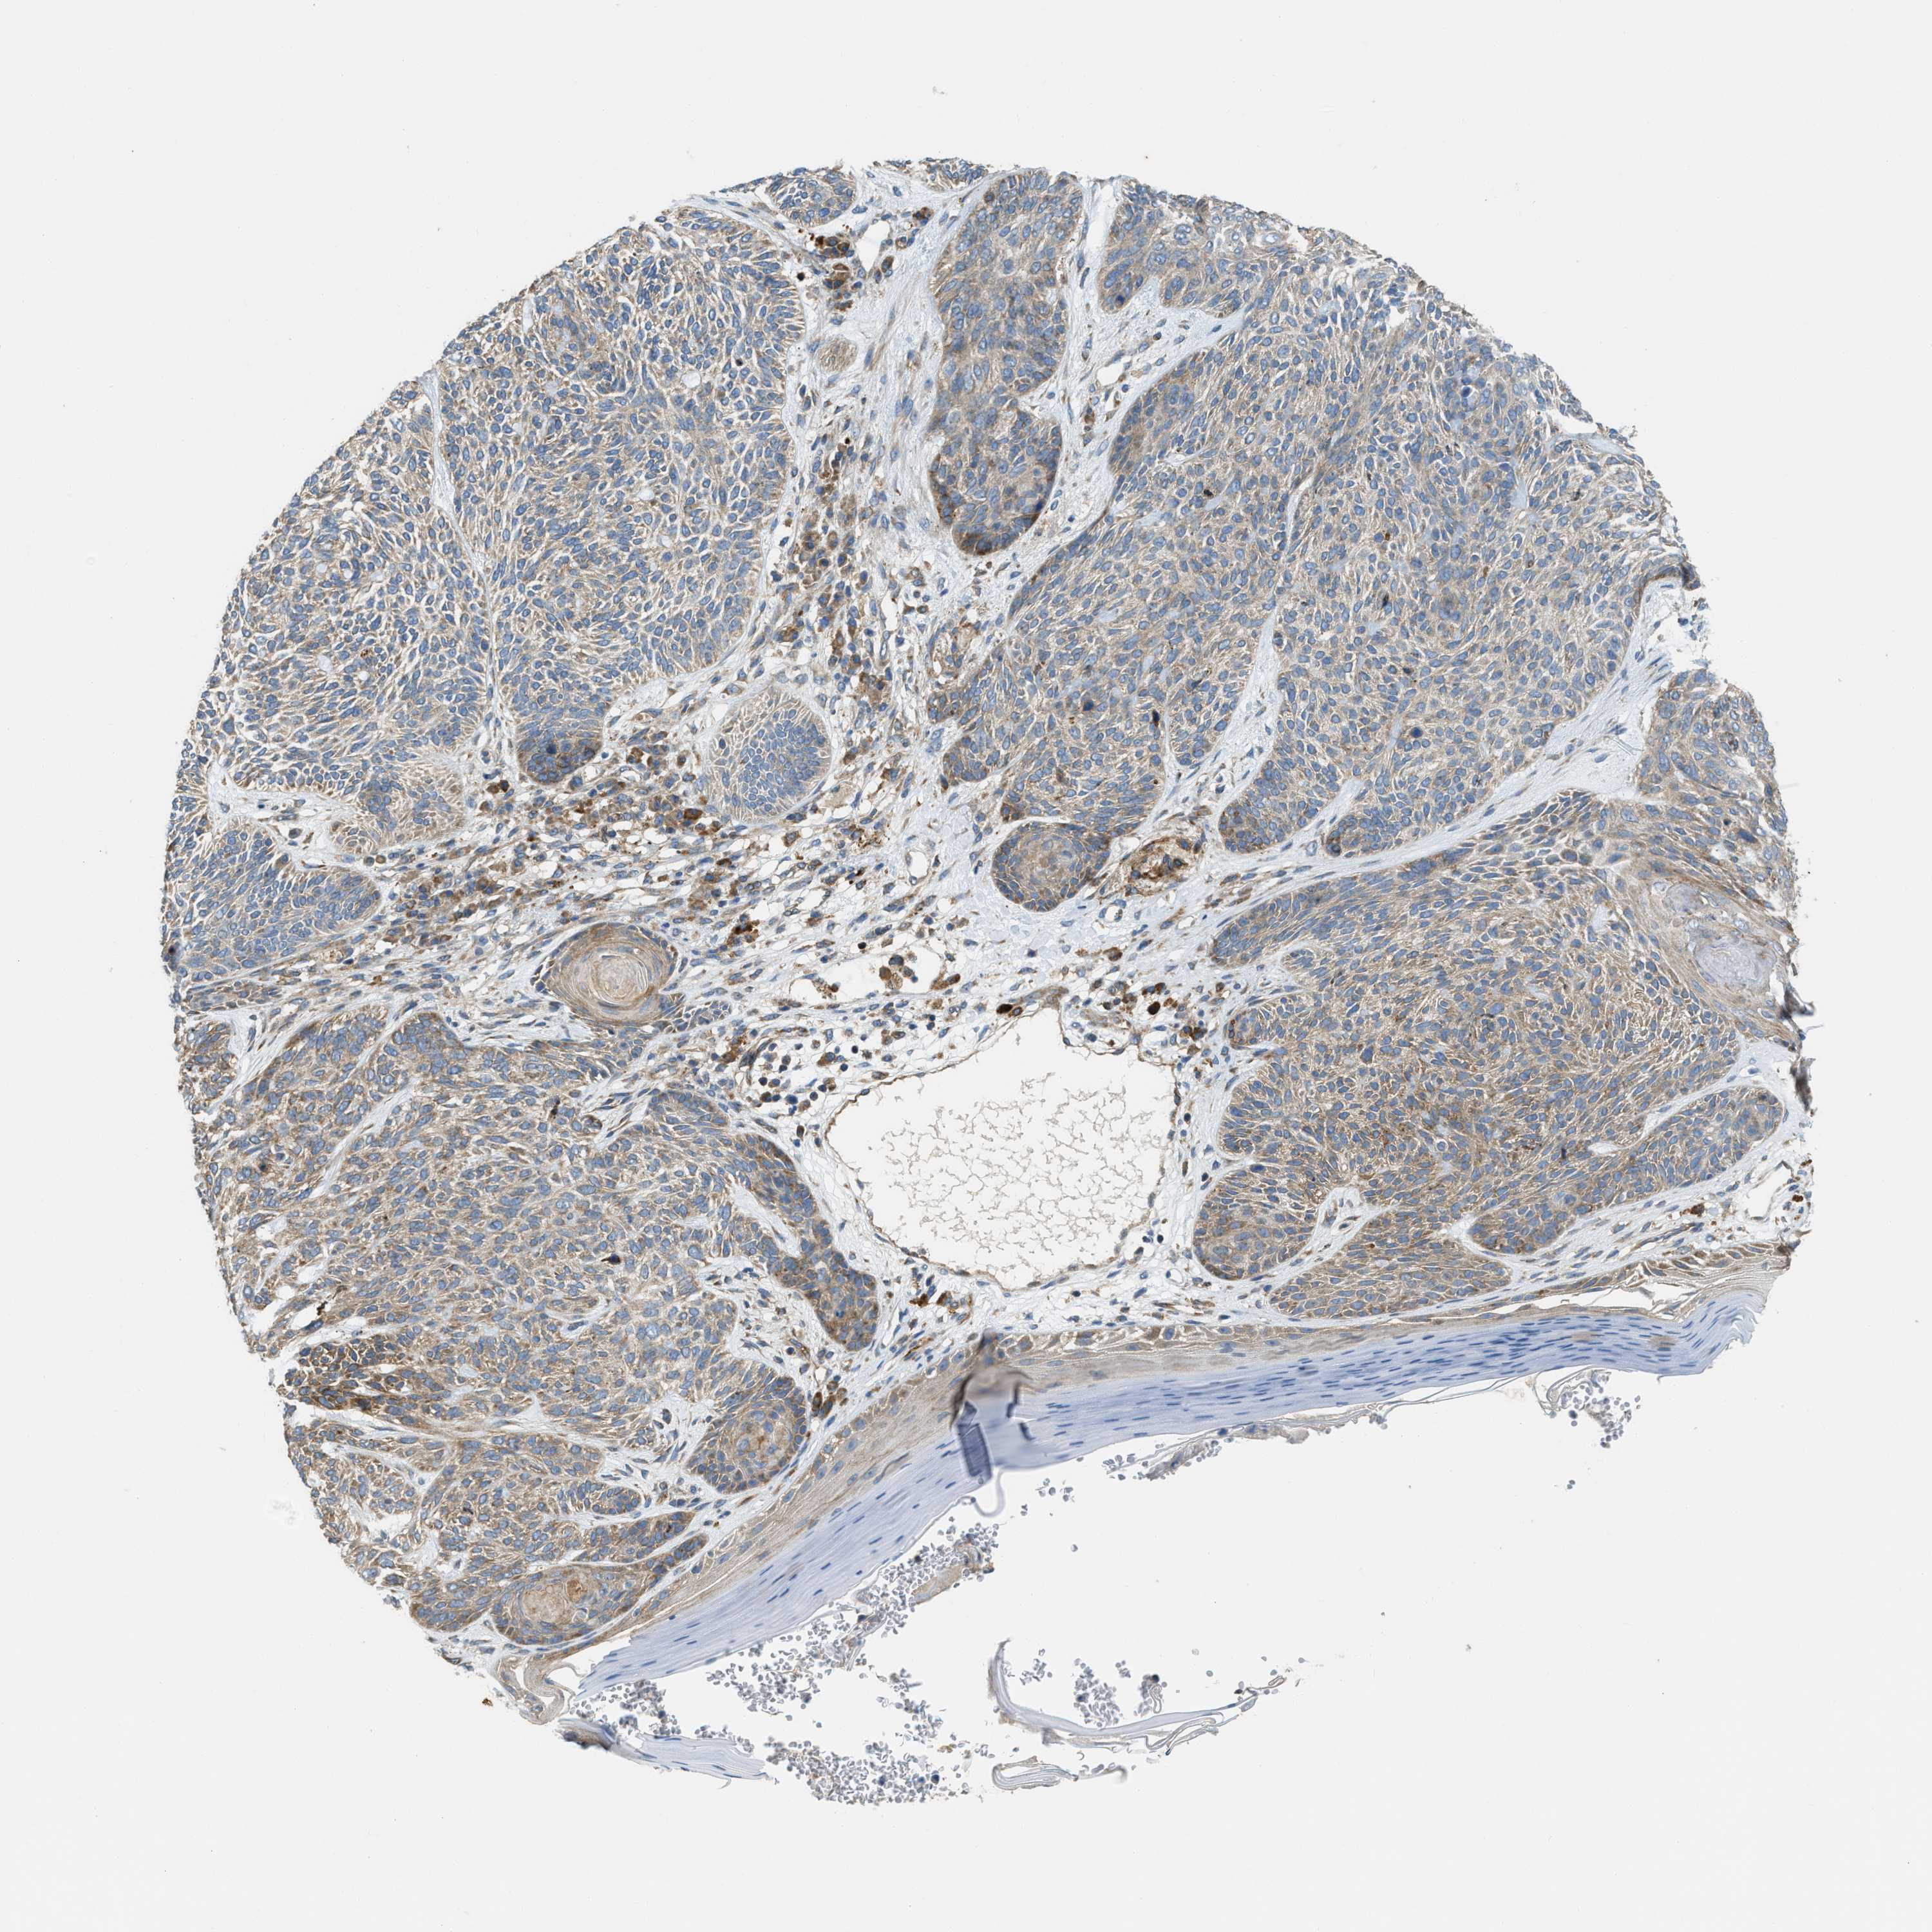

SKIN CANCER - Protein expressioni

A mouse-over function shows sample information and annotation data. Click on an image to view it in a full screen mode. Samples can be filtered based on level of antibody staining by selecting one or several of the following categories: high, medium, low and not detected. The assay and annotation is described here.

Antibody stainingi

Antibody staining in the annotated cell types in the current human tissue is reported as not detected, low, medium, or high, based on conventional immunohistochemistry profiling in selected tissues. This score is based on the combination of the staining intensity and fraction of stained cells.

Each image is clickable and will lead to virtual microscopy that enables deeper exploration of all samples and also displays staining intensity scores, fraction scores and subcellular localization as well as patient and tissue information for each sample.

Antibody HPA018216

Antibody HPA019173

Staining

High

Medium

Low

Not detected

Intensity

Strong

Moderate

Weak

Negative

Quantity

>75%

75%-25%

<25%

None

Location

Nuclear

Cytoplasmic/membranous

Cytoplasmic/membranous,nuclear

Squamous cell carcinoma in situ, NOS

Squamous cell carcinoma, NOS

Squamous cell carcinoma, metastatic, NOS

Basal cell carcinoma